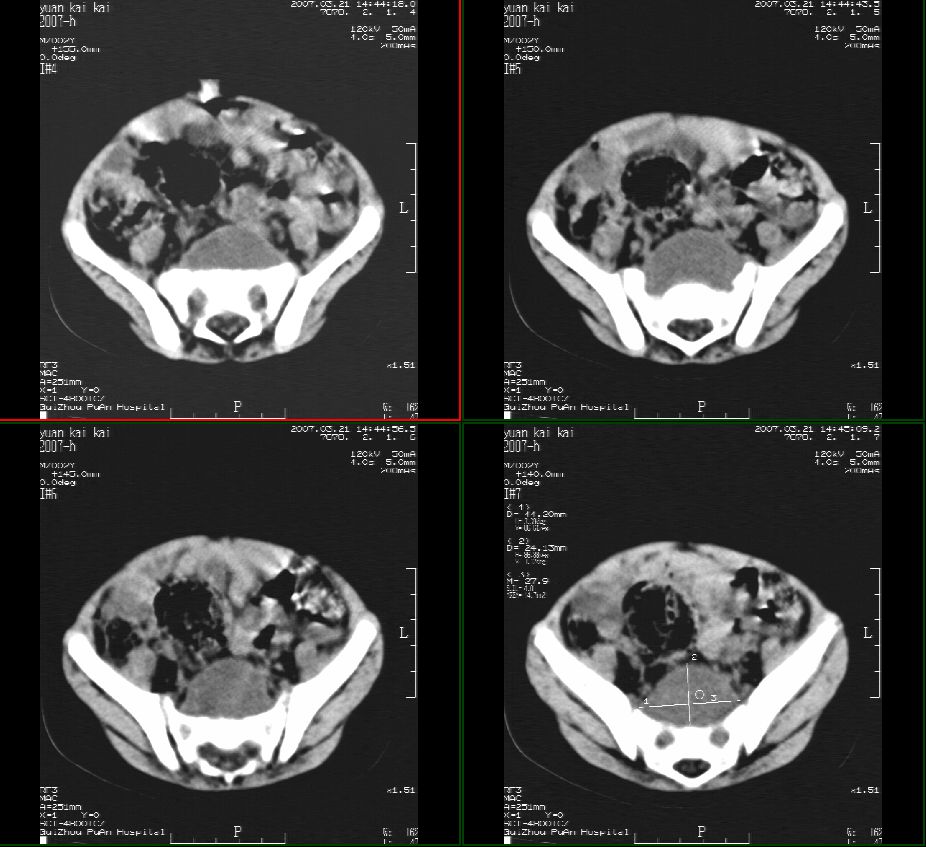

男性,2岁半,髋部疼痛10月,伴跛行,请大家会诊!

骶骨无明显吸收破坏征像,骶前见囊性占位,考虑:骶前脊膜膨出。

1骶前软组织畸胎类肿瘤。2,神经源性肿瘤。3,骶前脊髓膜膨出。

骶前脊膜膨出(anterior sacral meningocele):位于腰骶交界处有先天椎体缺失,膨出的硬脊膜和蛛网膜通过骶骨腹侧缺损,向骶前膨出,称骶前脊膜膨出。囊内一般无神经组织,有时神经根也会疝入到囊腔内,产生临床症状。而此患者椎体未见椎体缺损。